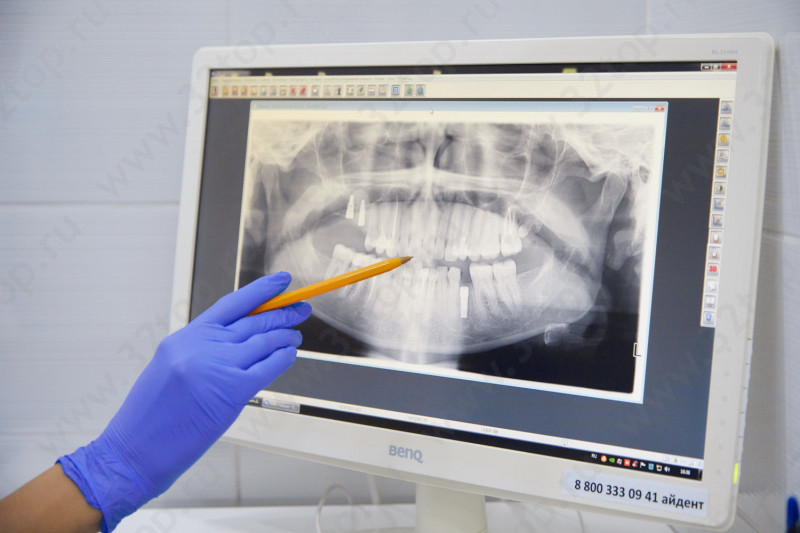

Есть рентген